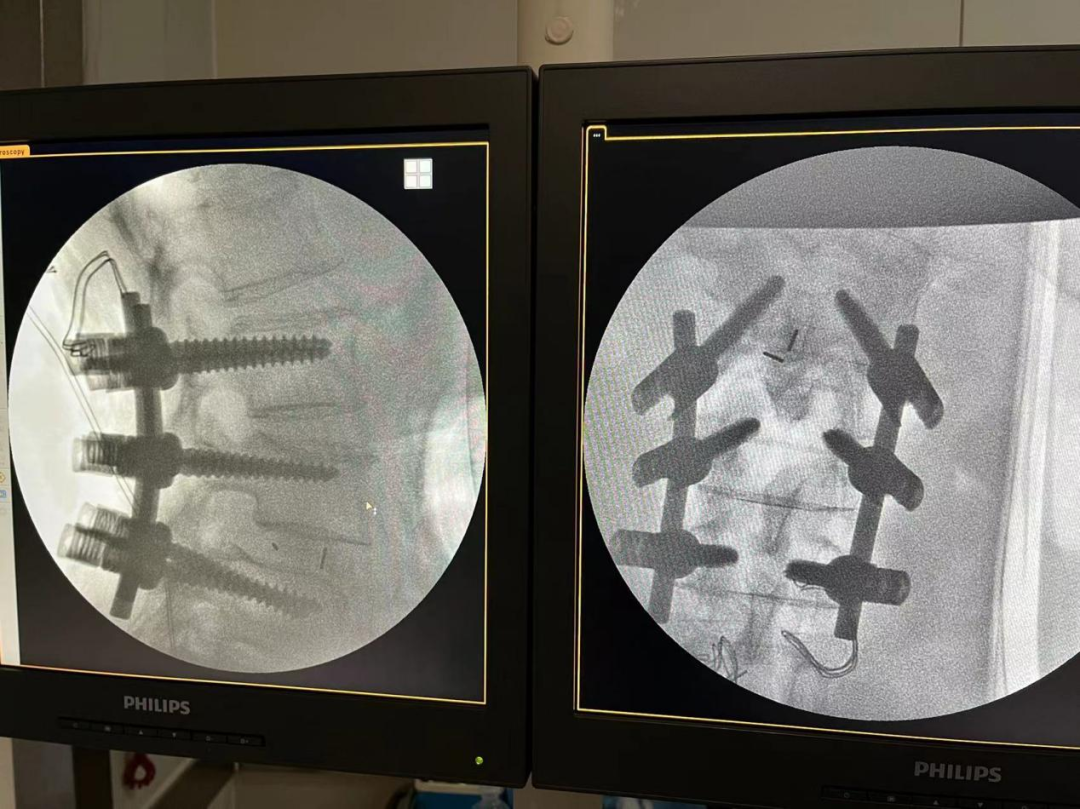

患者王婆婆已經(jīng)71歲了,近13年來反復(fù)腰部伴雙下肢疼痛無力,保守治療無效,近期尤為明顯,行走幾百米就小腿脹痛明顯,無法繼續(xù)走路,嚴(yán)重影響日常生活。加之子女遠(yuǎn)在國外,無法照顧王婆婆,她輾轉(zhuǎn)多個(gè)三甲醫(yī)院,最后選擇轄區(qū)較近的我院外科入住。入院后外科積極進(jìn)行圍手術(shù)期管理,醫(yī)患溝通,嚴(yán)格落實(shí)核心制度。完善相關(guān)檢查,診斷為腰4椎體骨折并滑脫、椎管狹窄。外科結(jié)合術(shù)前的各項(xiàng)檢查,細(xì)致的術(shù)前討論,制定了合理的手術(shù)方案,最終決定為患者實(shí)施“腰3-5置入椎弓根螺釘,腰4-5椎板切除減壓椎間植骨融合復(fù)位釘棒內(nèi)固定術(shù)”,歷經(jīng)3小時(shí),手術(shù)順利完成,術(shù)中出血僅300ml,,術(shù)后患者雙下肢感覺運(yùn)動(dòng)正常,腰腿疼痛立即緩解?;颊邔?duì)治療效果非常滿意。術(shù)后第3天已經(jīng)下床行走,春節(jié)前即將順利出院,過一個(gè)真正快樂、毫無病痛的春節(jié)!

腰椎后路滑脫椎管減壓植骨融合內(nèi)固定術(shù)是脊柱外科常用的手術(shù)方式之一,其手術(shù)方法主要是經(jīng)腰椎后路打開椎管,松解粘連、緊張的神經(jīng)組織,切除病變突出的腰椎間盤,并植入椎間融合器及內(nèi)固定裝置,從而達(dá)到解除神經(jīng)壓迫,緩解腰椎間盤壓力,重建脊柱穩(wěn)定,降低患者復(fù)發(fā)率的目的。適用于腰椎間盤突出癥導(dǎo)致的腰腿部麻木、疼痛等不適,或腰椎間盤突出癥病情反復(fù)發(fā)作或者久治不愈,以及存在腰椎節(jié)段性不穩(wěn)導(dǎo)致的腰椎滑脫、腰椎管狹窄癥、脊柱側(cè)彎畸形、馬尾神經(jīng)疼痛等腰椎疾病。